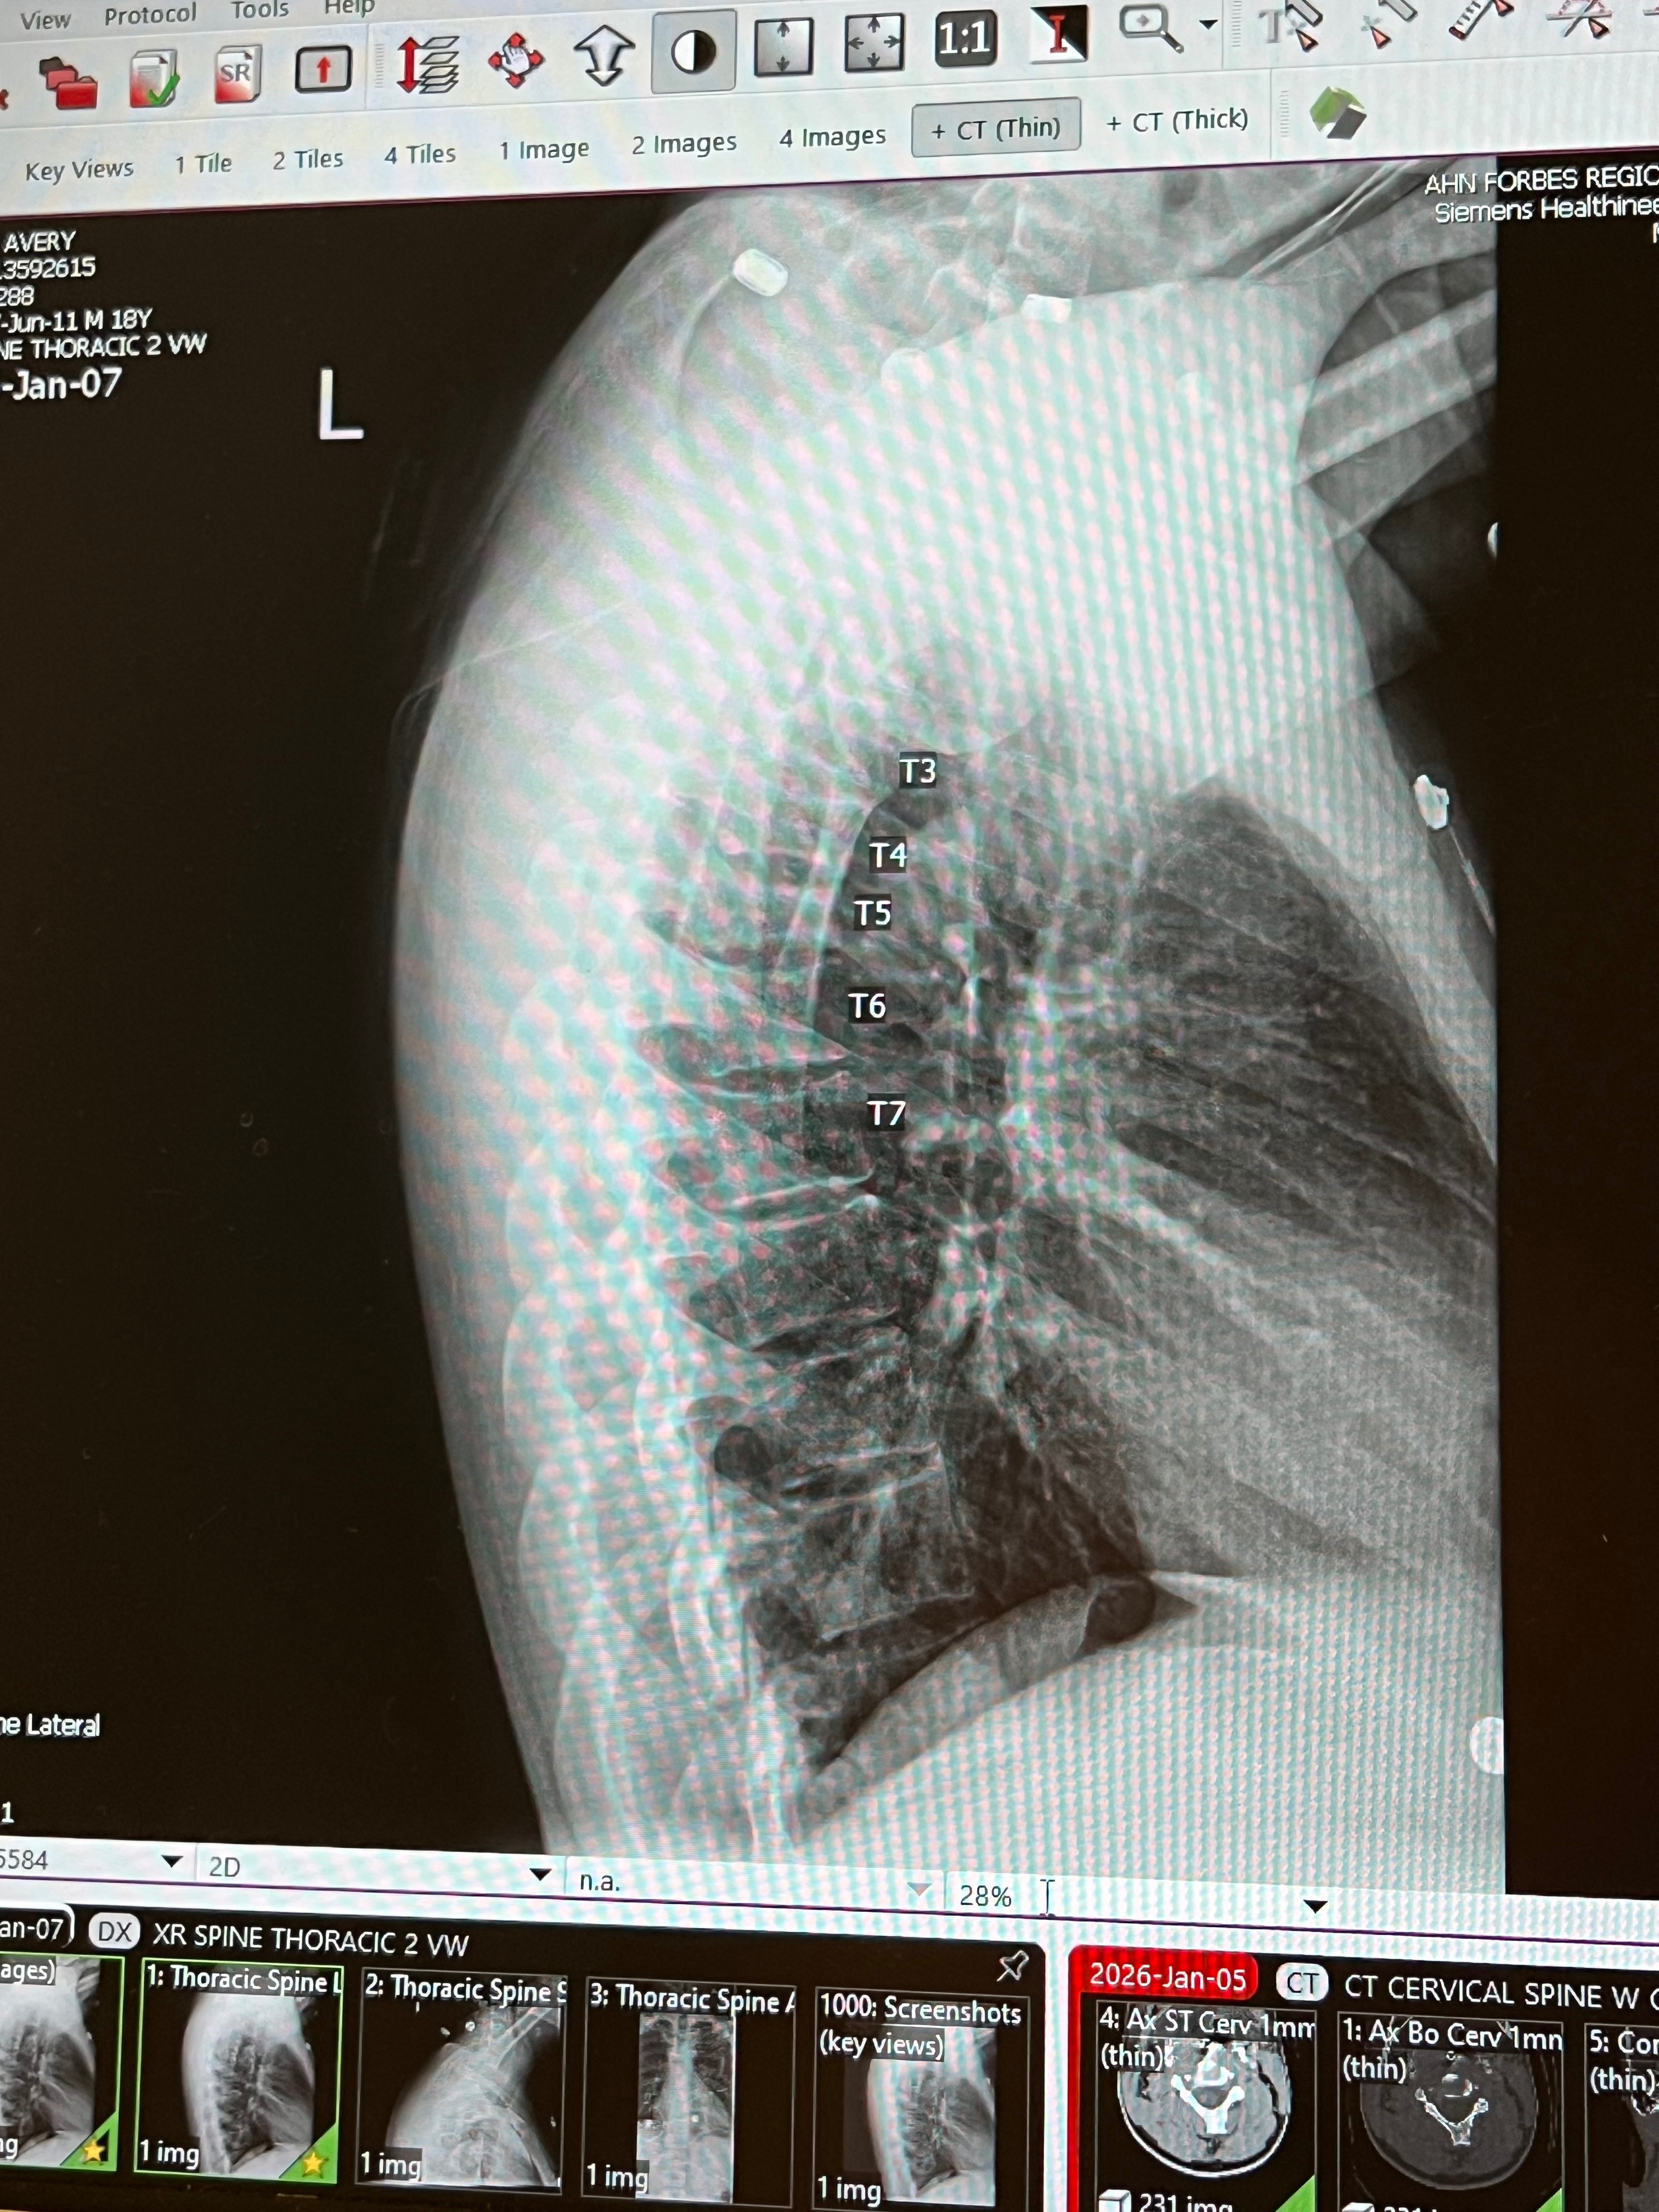

Instead of planning his future, Avery spends his days in pain and fear. He lives with frequent seizures, two tumors in his brain, and a broken back that makes even the simplest movements exhausting. His body doesn’t give him breaks, and neither does life.

There are moments when Avery is scared to fall asleep, afraid a seizure will come and no one will be there to help. The pain in his back never fully fades. The headaches remind him every day that the tumors are still there. This is not something anyone—especially someone so young—should have to endure.